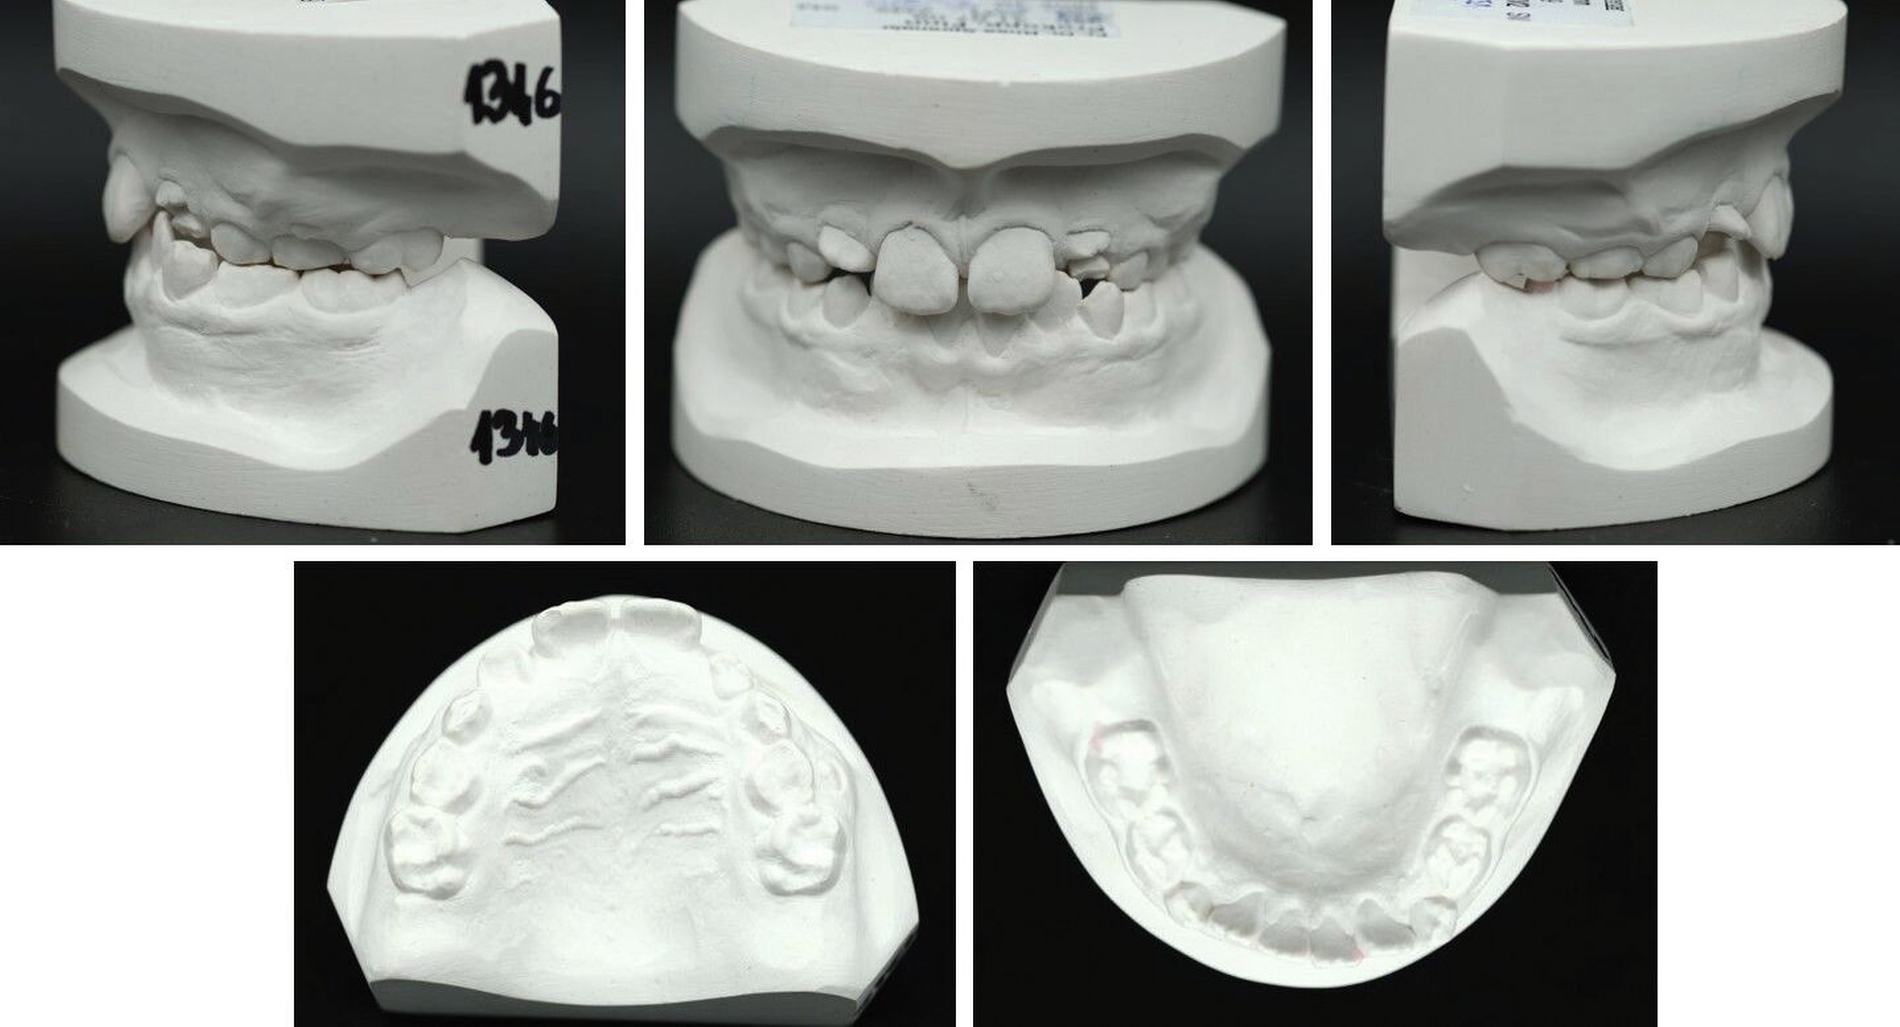

Ein zwölfjähriger Patient stellte sich in der Poliklinik für Kieferorthopädie des Universitätsklinikums Tübingen mit einer skelettalen Klasse-III-Konfiguration, einer Angle-Klasse III, einem Kreuzbiss auf der linken Seite und transversal schmalem Oberkiefer vor. Die Anamnese ergab ein vermindertes Hörvermögen, weshalb der Patient Hörgeräte trug. Darüber hinaus wurde keine Medikamenteneinnahme oder Allergie angegeben. Er wies mit einem dentalen Alter von sieben Jahren einen verzögerten Zahndurchbruch auf. Der initiale intraorale Befund zeigte die in situ befindlichen Zähne 11, 21 und 32–42. Die Zähne 12 und 22 eruptierten in Inklinationsfehlstellung. Die Milcheckzähne und -molaren befanden sich noch in situ. Die Sechsjahrmolaren waren nicht eruptiert und zeigten eine Verlagerungstendenz, insbesondere im Unterkiefer (Abbildung 1, Tabelle 1).

Die initiale Panoramaschichtaufnahme zeigte die Verlagerung mehrerer Zahnkeime sowie einen Platzmangel der Eckzähne und der Prämolaren im Oberkiefer (Abbildung 1b). Die Keimkrone von Zahn 13 wies dabei eine enge Lagebeziehung zum Zahnkeim 12 auf (Abbildung 1b). Die bereits eruptierten permanenten Frontzähne zeigten eine Angulations- und eine Inklinationsfehlstellung. Im distalen Bereich waren keine Durchbruchshindernisse erkennbar. Vor Beginn der kieferorthopädischen Behandlung wurde eine Primäre Zahndurchbruchsstörung (Primary Failure of Eruption – PFE) genetisch ausgeschlossen.